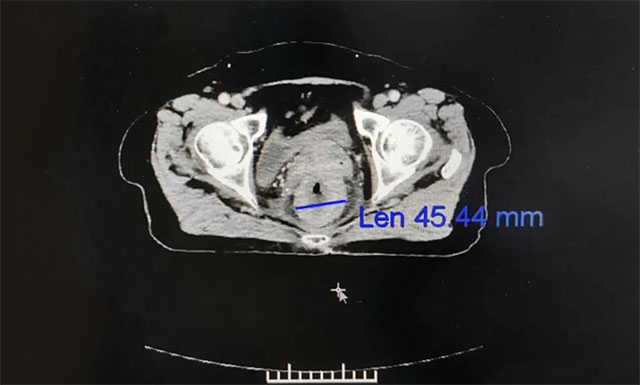

▲ 放療后患者病灶縮小,病癥逐漸緩解

隨后,劉女士在醫(yī)院進行一個療程的放療治療,放療期間未見明顯不良反應(yīng),恢復良好。對于這次放療效果,李女士還是很滿意的,她講道:“經(jīng)過這次放療,之前肛門處流脹、里急后重及墜脹的癥狀明顯改善,現(xiàn)在夜里終于無便意,可以一覺睡到天亮,這種感覺真是太好了,而且在醫(yī)院這一個多月我竟然還胖了3斤,現(xiàn)在心情也好了很多,特別感謝藍十字放療科的所有醫(yī)護人員們”。